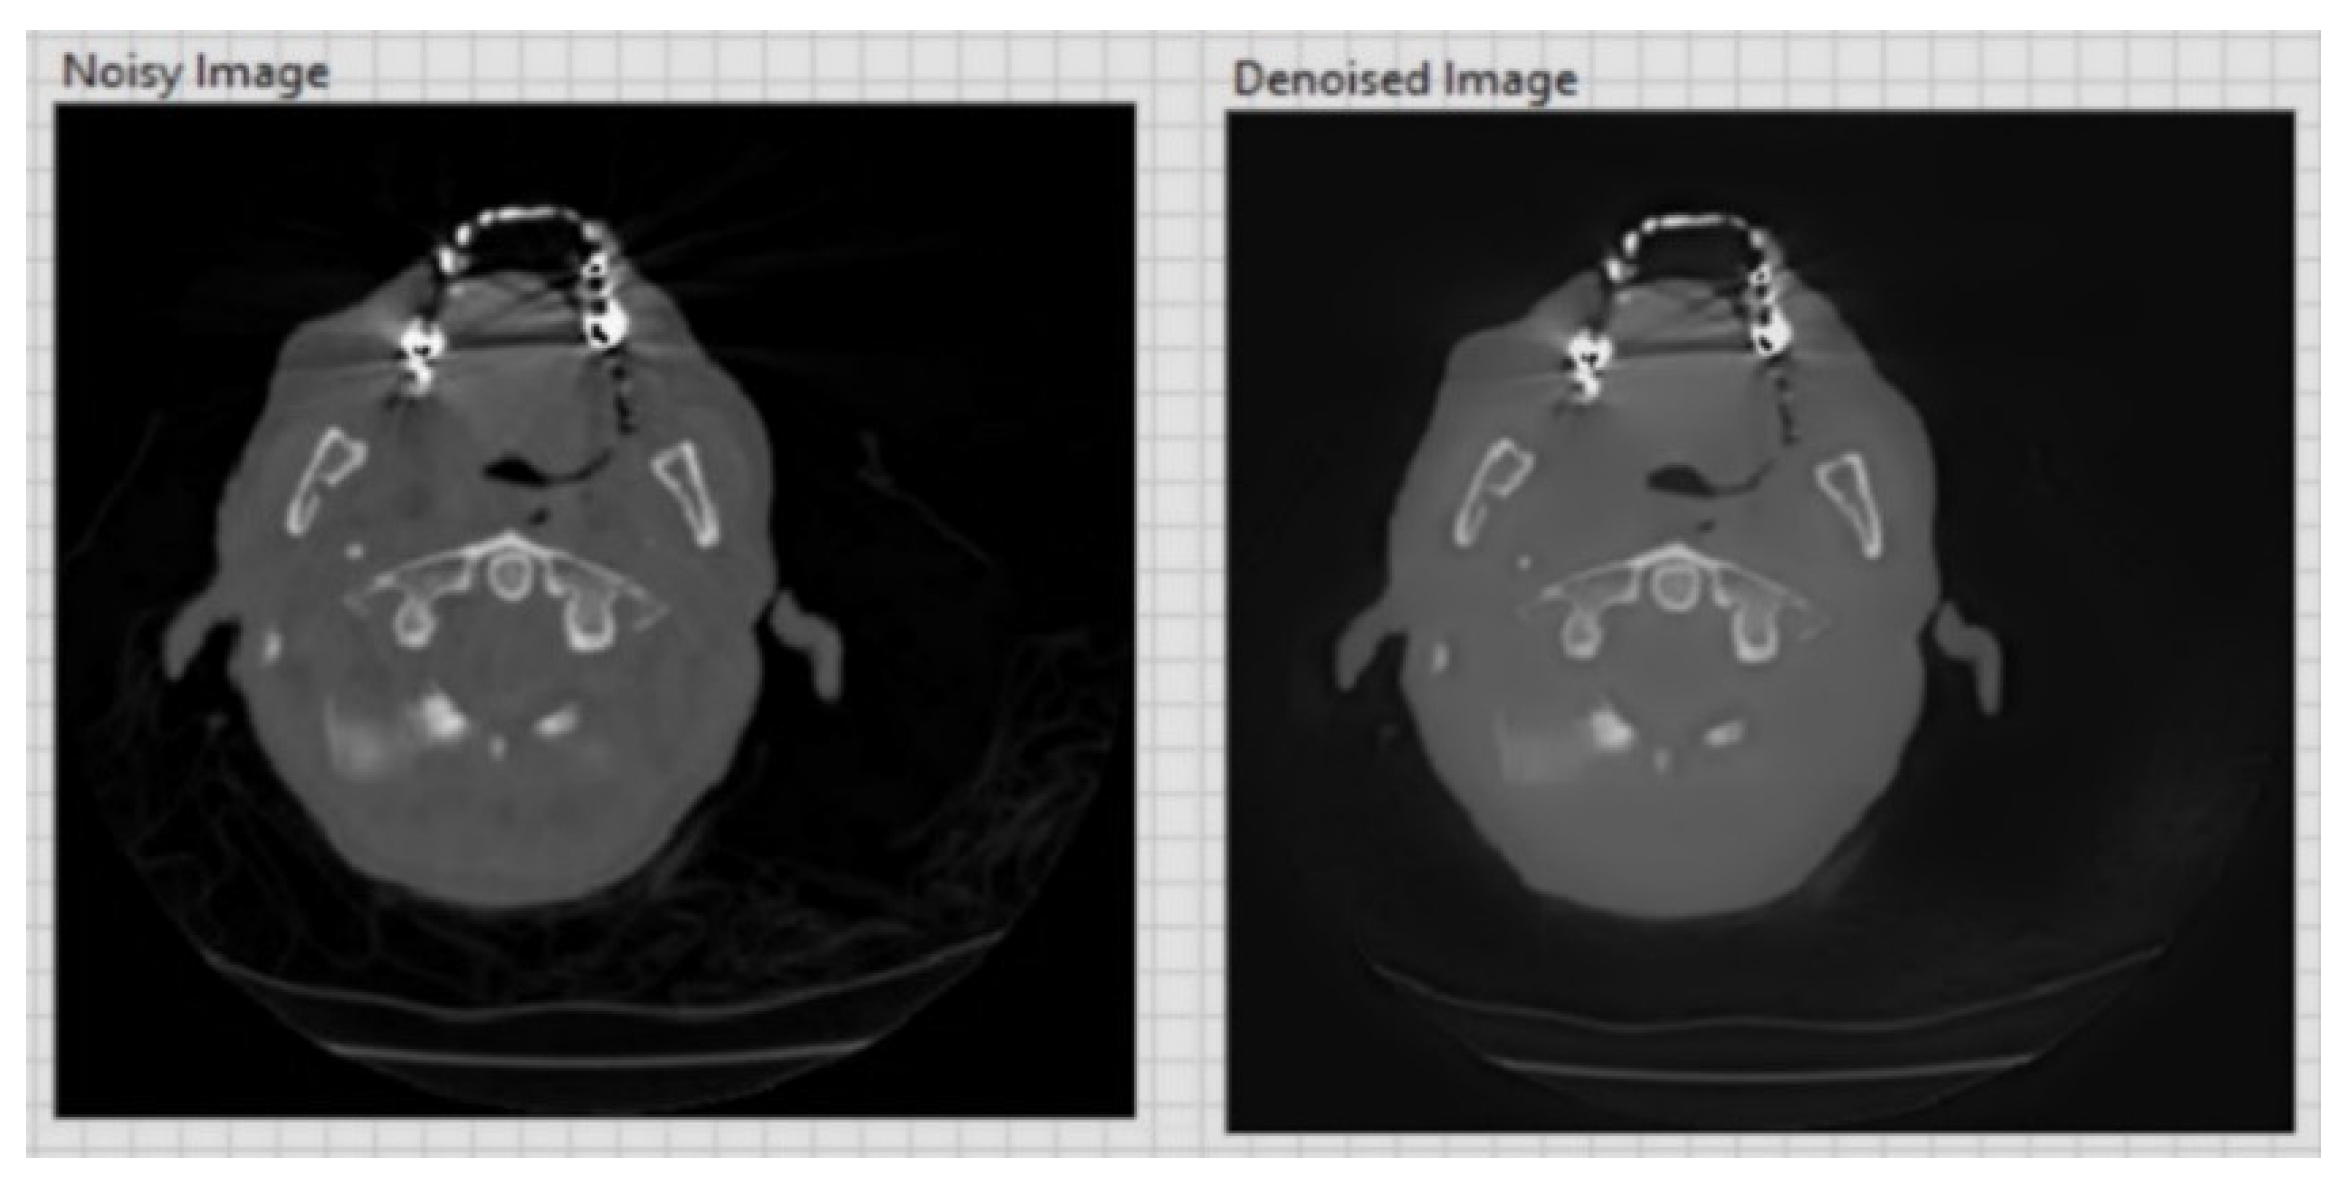

| CT image (Figure 6) 256 × 256 | 26.01 | 0.05 |

| CT image (Figure 7) 256 × 256 | 20.15 | 0.1 |